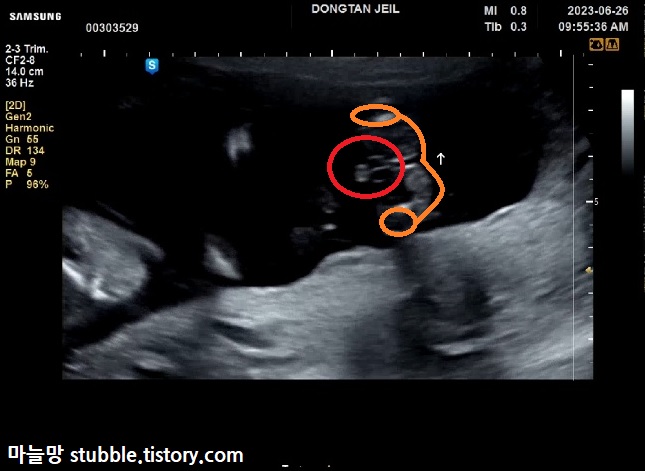

이건 제가 캡쳐 해놓고도 한참을 이게 뭔가 하고 봤네요.

구순열 여부를 살짝만 (맛보기로) 본 것 같아요. 자세한 건 정밀초음파를 봐야 알겠지만요.

화면 나오자마자 정면에서 너무 또렷하게 보여서 신랑이 먼저 「보이네요!」라고 말했고, 담당쌤 웃으시고 아무 말하지 않으셨어요.

아들맘 확정입니다.